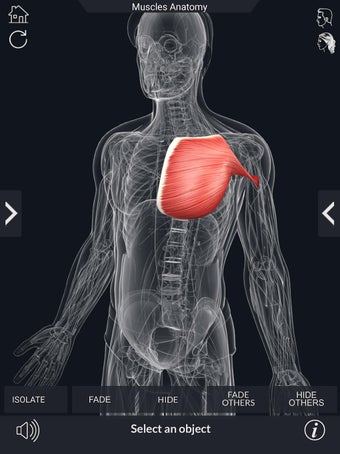

Det finns många verktyg tillgängliga för varje muskel, inklusive:

- Göm och visa varje muskel separat.